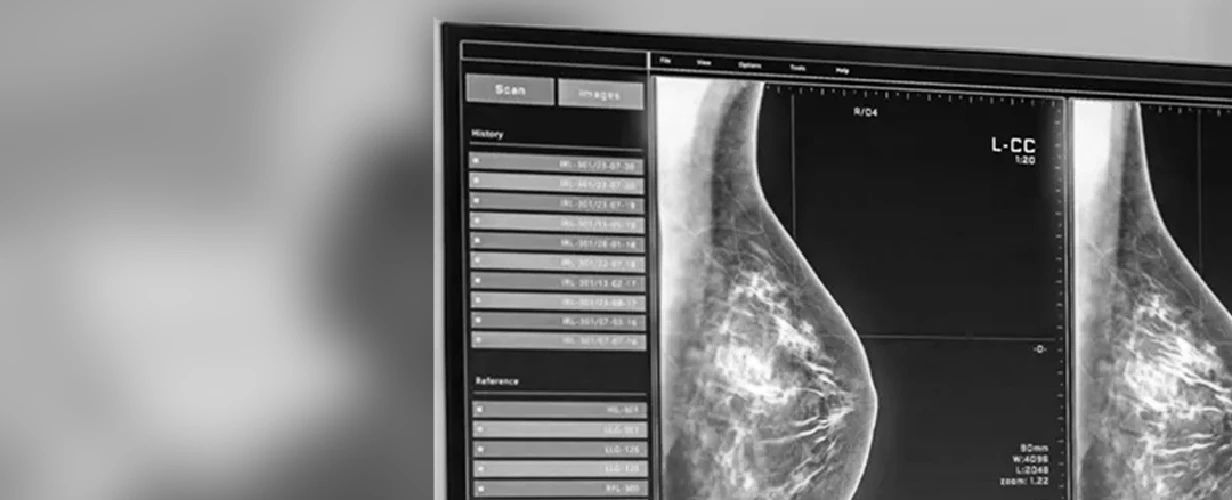

Screening is personalized for each woman's age, history, and risk profile. Depending on your case, I may recommend a mammogram, breast ultrasound, or MRI – or a combination of these – to ensure the most accurate and comprehensive assessment possible.